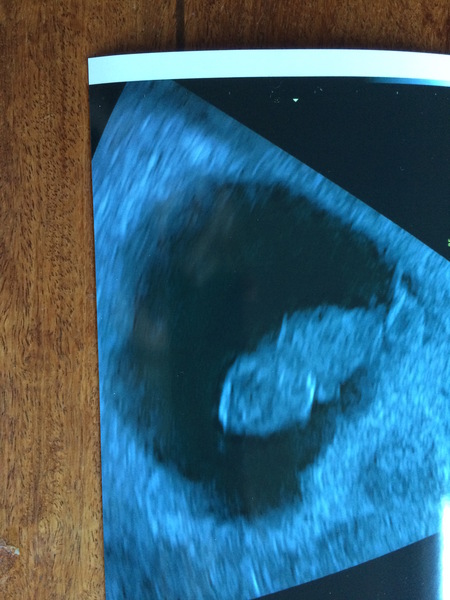

MOGMOGMOG85 · 06/05/2020 19:28

My scan went well! I'm measuring 4 days ahead which is impossible because I didn't have sex until 2 days after conception in that case... but anyway what amazing news. I was shaking when she located the pregnancy (which was immediately - so different to last time)!!

Feeling a bit crampy now after the ultrasound, has anyone else had this?

:) thank you to everyone for all your endless support during that difficult time before I knew there was anything there xxx